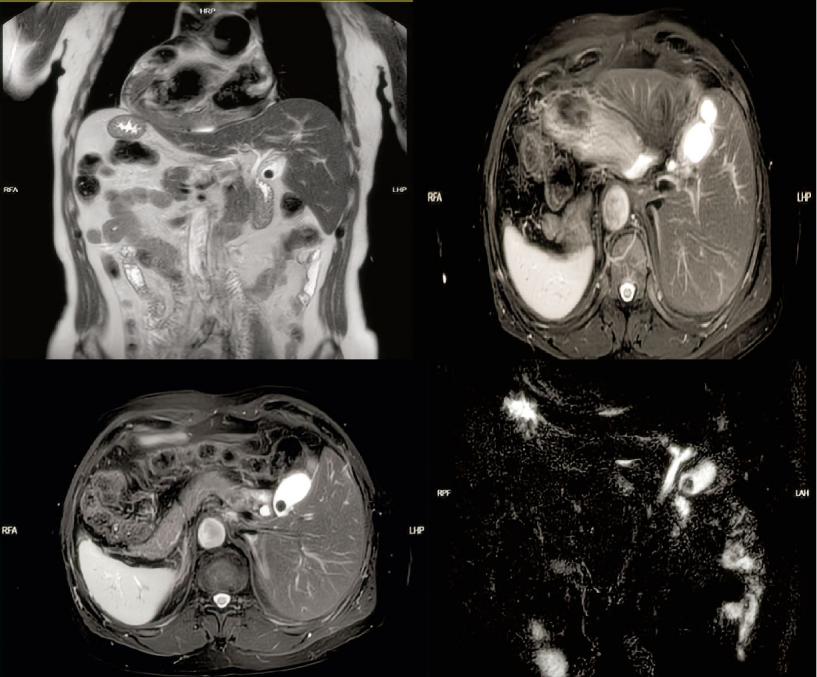

患者完善相关检查后,董晓勇组织了影像科、心内科、麻醉科、医务科相关科室开展MDT讨论,详细分析患者病情,精准标注胆囊位置、大小、病变范围及周围血管、胆管走向,对反位脏器进行精准解读,提出专业性的意见,保障手术顺利完成。在李海锋主治医师与患者及家属进行充分沟通后,决定实施“全内脏反位胆囊结石伴胆囊炎”手术。

上腹部核磁+MRCP影像 (左侧胆囊)